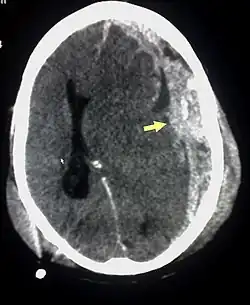

| Субдуральная гематома (обозначена стрелкой) со значительным смещением срединных структур. | |

При компьютерной томографии субдуральные гематомы имеют классическую серповидную форму, однако, могут выглядеть и линзовидно, особенно в начале кровотечения; это может вызвать затруднения в дифференциальной диагностике субдуральной и эпидуральной гематом. Более достоверным признаком субдуральной гематомы является её относительно большая распространённость по ходу полушария головного мозга с преодолением швов черепа, в отличие от эпидуральной гематомы. Субдуральная гематома также может выглядеть как «наслоение» повышенной плотности по ходу намёта мозжечка; такая гематома может быть хронической и стабильной, и косвенными минимальными признаками кровоизлияния могут служить сглаженность прилегающих борозд и медиальное смещение границы между серым и белым веществом.